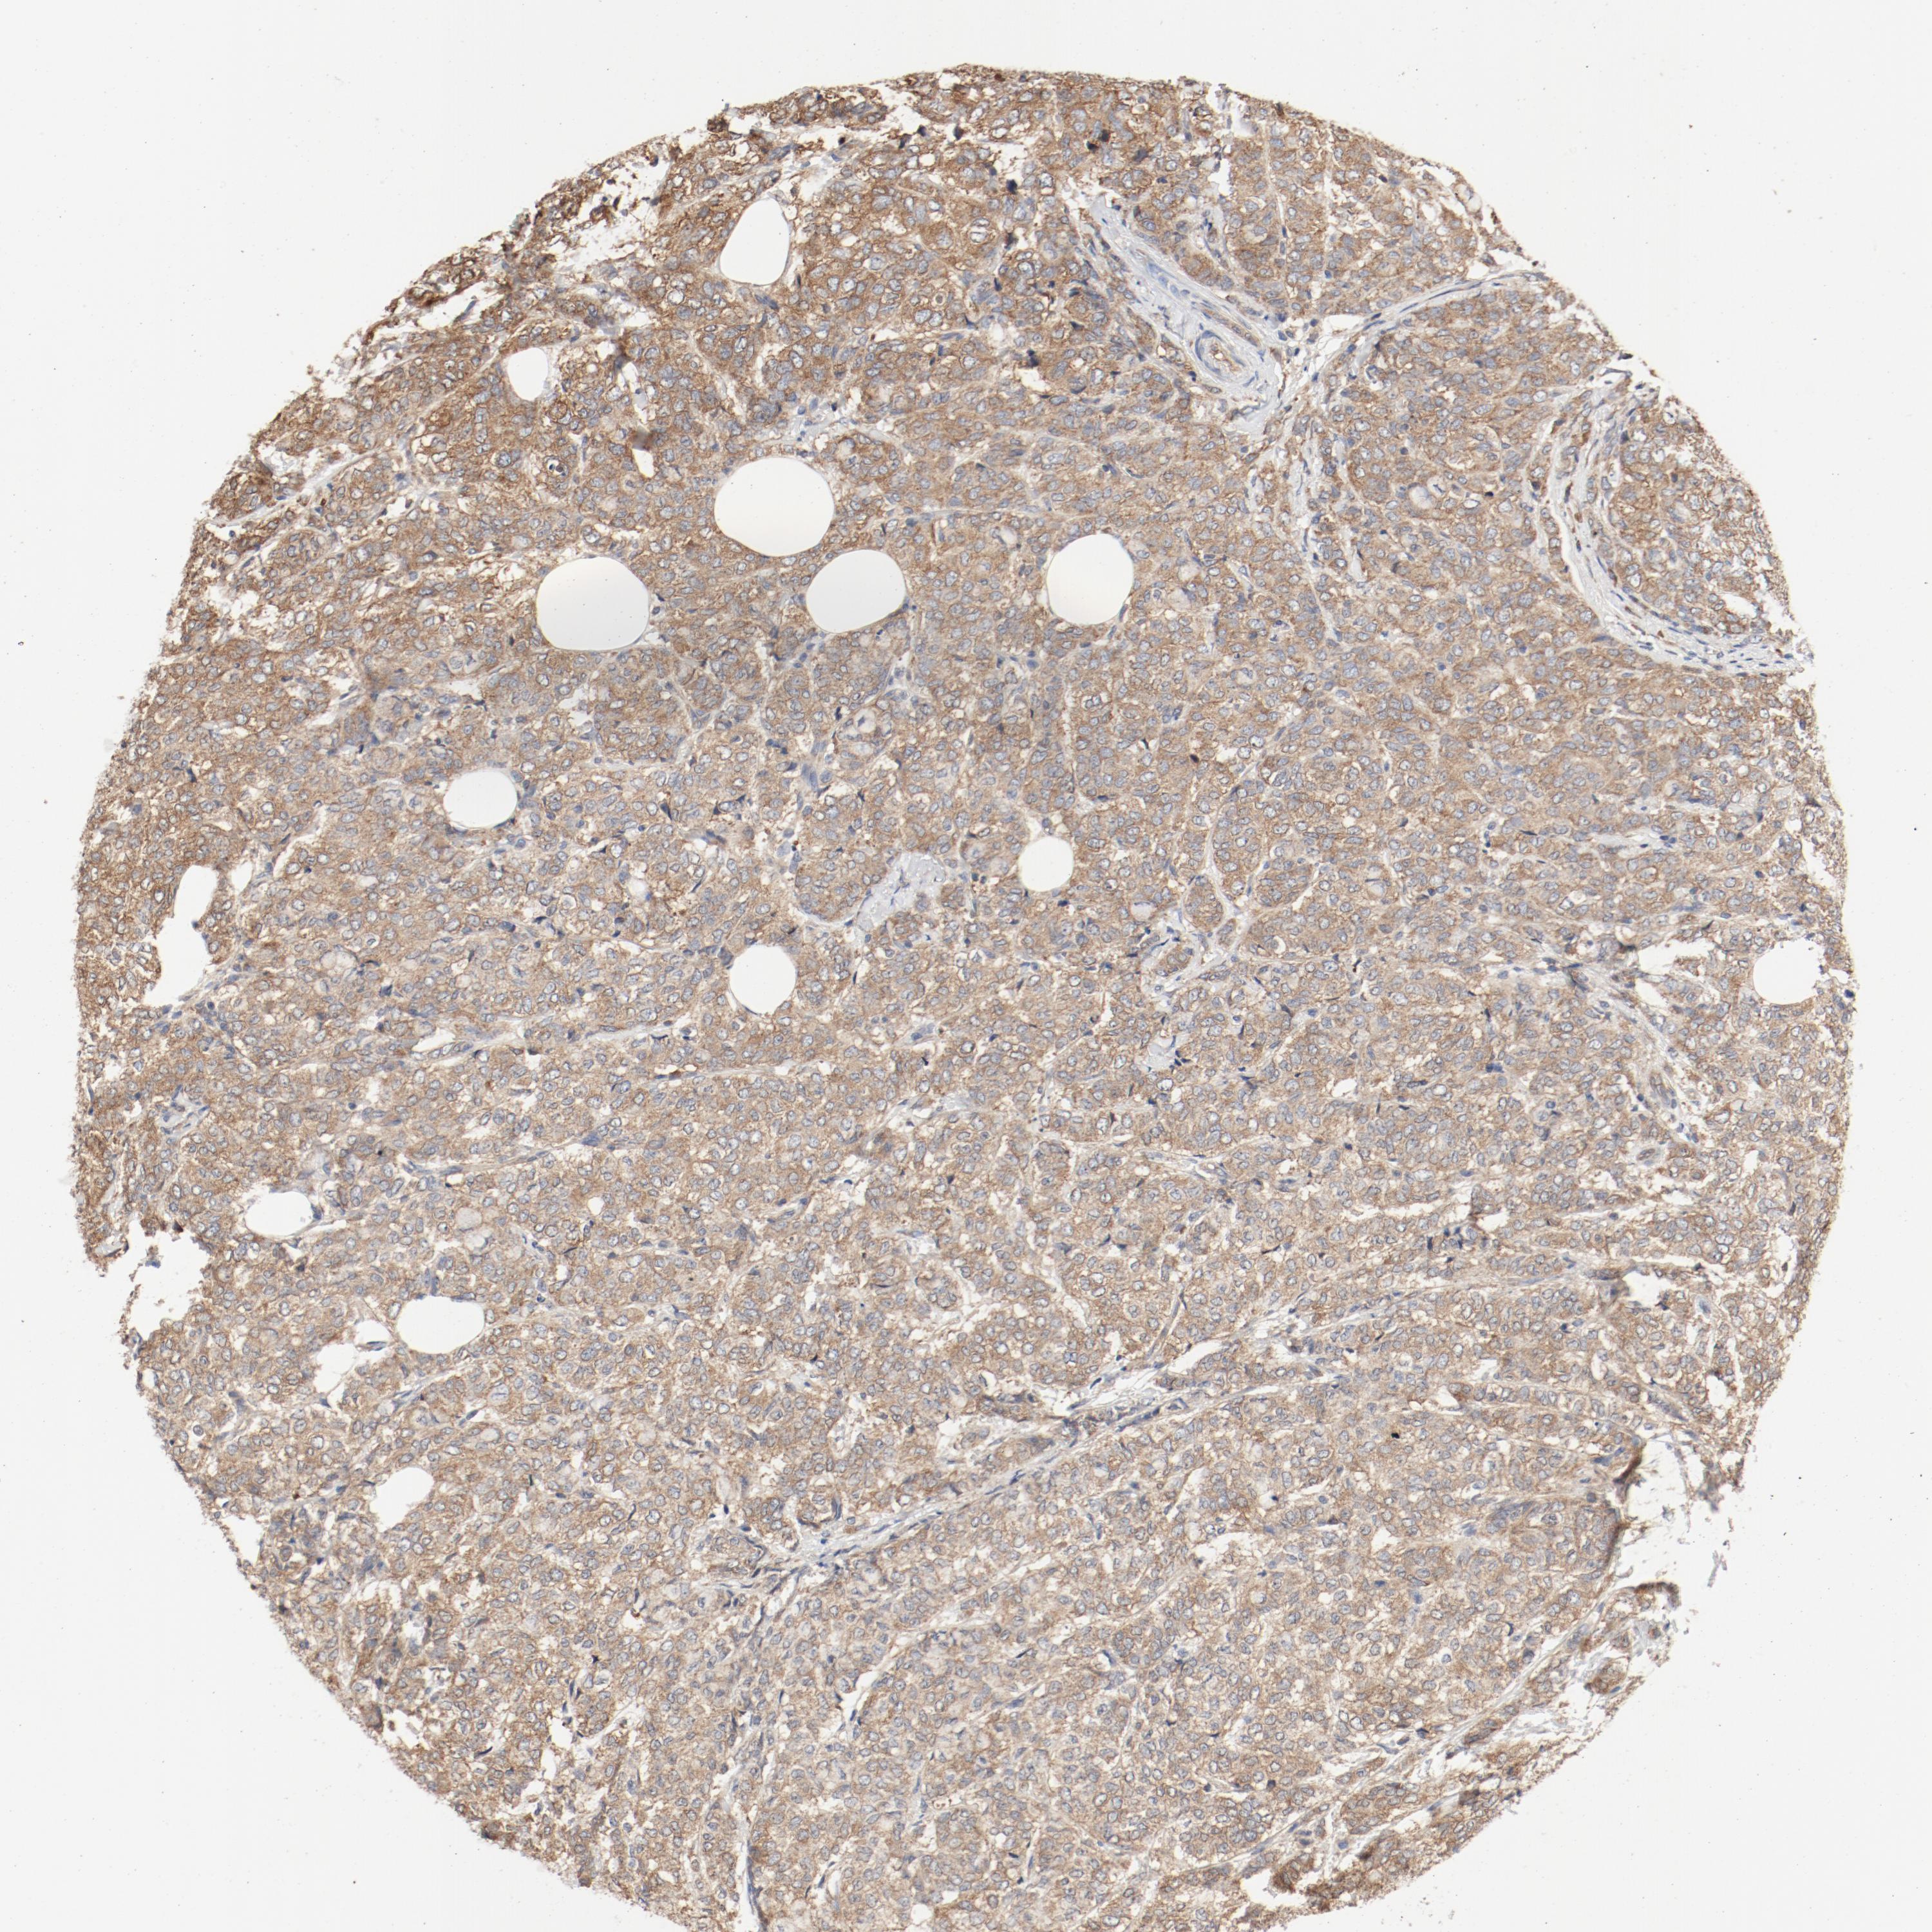

CANCER BREAST CANCER Show tissue menu

BRCA TCGA BRCA VALIDATION PROTEIN EXPRESSION